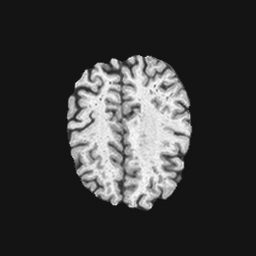

Exp. 2: Fetal brain data is used to test the robustness of our approach under real conditions. Fetuses younger than 30 weeks very often move a lot during examination. Fast MRI sequences allow artifact free acquisition of individual slices but motion between slices corrupts consistent 3D information. Fig. 3 shows that our method is able to accurately predict also under these conditions. For this experiment we use from three orthogonally overlapping stacks of ssFSE slices covering the fetal brain with approximately 20-30 slices each. We are ignoring the stack transformations relative to the scanner and treat each individually. For , 28 clinically approved motion compensated brain reconstructions are resampled into a volume with spacing. A density of 500 unique sampling normals has been chosen via the Fibonacci sphere sampling method with 25 sampling planes evenly spaced between -25 to +25 on the Z-axis. This gives a plane spacing of 2mm, sampling only the middle portion of the fetal brain. Training took approximately 10hrs for 30 epochs. Prediction, i.e., the forward pass through the network, takes approx. 12 ms/slice.

0..5 Randomly selected illustrative inference results

Here we show for Exp. 1, Exp. 2, and Exp. 3 randomly selected examples of images that have been presented to the network (ground truth) compared to an image sampled at the predicted location.

In these experiments, we present a ground truth (GT) image to the network to estimate the respective transformation parameters needed to reorient the slice in its correct world co-ordinates. Using the transformation parameters, we generated a slice from the 3D atlas in the location where the network has predicted that slice should be (denoted as SVRNet).

The slices are compared side-by-side to give a visual representation of “where the slice really is” and “where the network thinks the slice is”.

0..5.2 Exp. 2:

Slices, from a motion corrupted MRI stack, are segmented and cropped. Since there is no ground truth for the queried images, an arbitrary fetal atlas is used for visualization in Fig. 11 and 12.